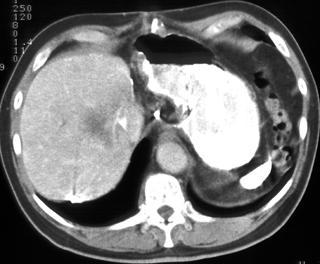

Biliary cystadenoma